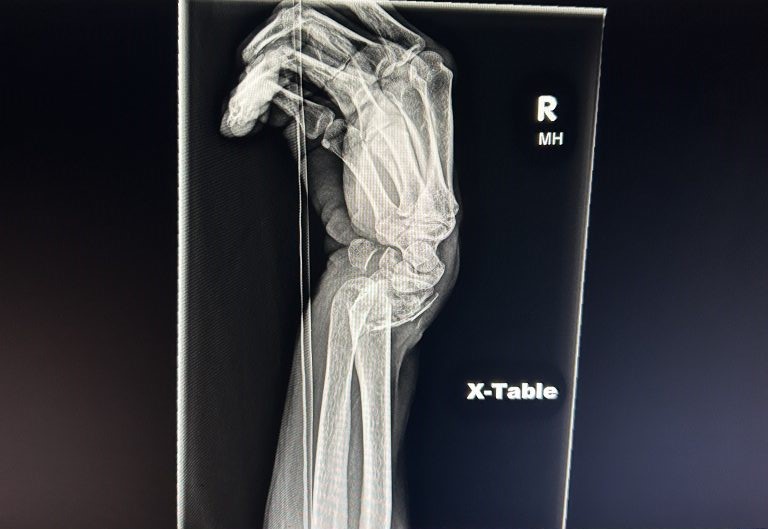

My wrist was deformed. My hand was over there and the rest of my arm was over here, like the letter S (see image). It was like something out of a horror movie - but it was attached to me! The local ER drugged me then moved my hand back into place and told me to see a wrist surgeon in case I needed surgery. I visited two local surgeons in Bucks County, PA, and then went down to a facility in Philadelphia for a third opinion. The first doctor wanted to put me under general anesthesia, which I didn't want. The other two said they would do a local block with twilight anesthesia, which was fine; however, they all told me I needed metal hardware with multiple screws, and that scared the living daylights out of me. I had never had surgery before and, especially, not had any metal implants.